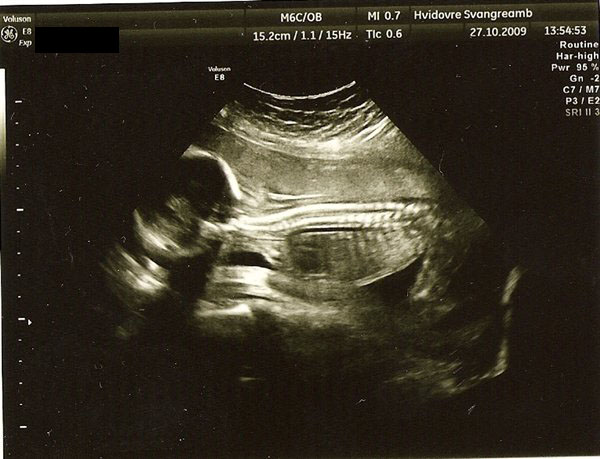

De første 2 billeder er fra nakkefoldescanningen (i uge 13), det næste er fra misdannelses scanningen i uge 20 og det sidste (og dårligeste) er fra den første hjerte scanning i uge 26.